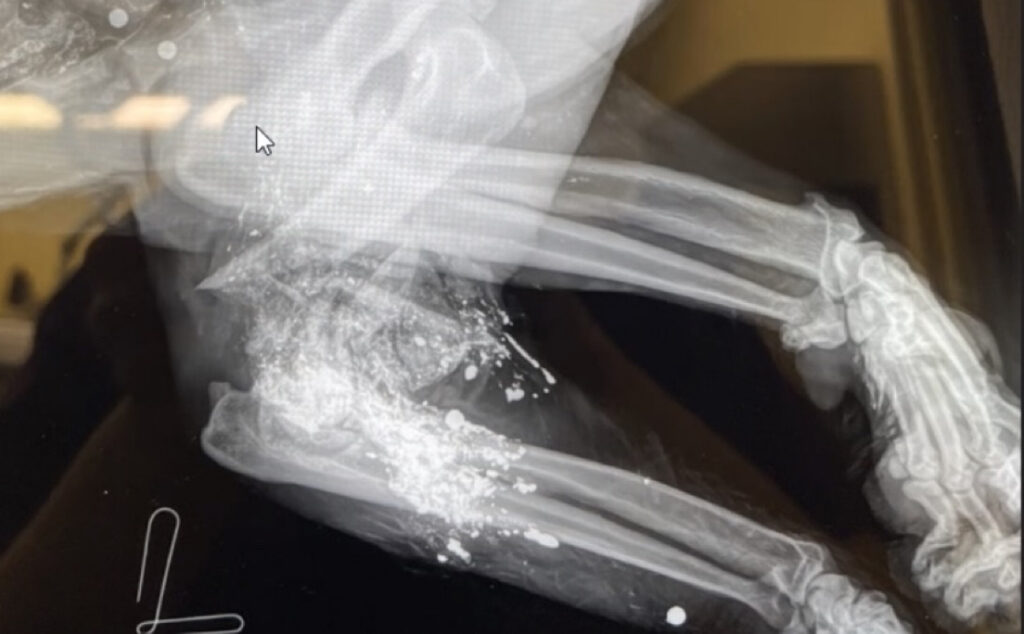

The case of the female mountain lion P1 is a prime example of displaying a dramatic shift toward livestock in her diet after being severely injured by gunshot. P1 was a 15–16-year-old female from the Sonoma Valley area who was killed after attacking a dog in someone’s house and killing livestock on the property. A necropsy conducted by the California Department of Fish and Wildlife (CDFW) showed that her elbow was completely shattered from a gunshot some time before, and she showed evidence of being shot on another occasion.

P33, a 3.5-year-old female whose home range includes Taylor Mountain Regional Park and parts of Trione-Annadel State Park, was limping badly from a gunshot wound when first captured and collared by the study. Fortunately, her gait appears normal again based on recent trail camera video footage and she is focusing on natural wild prey, suggesting the injury has healed well.